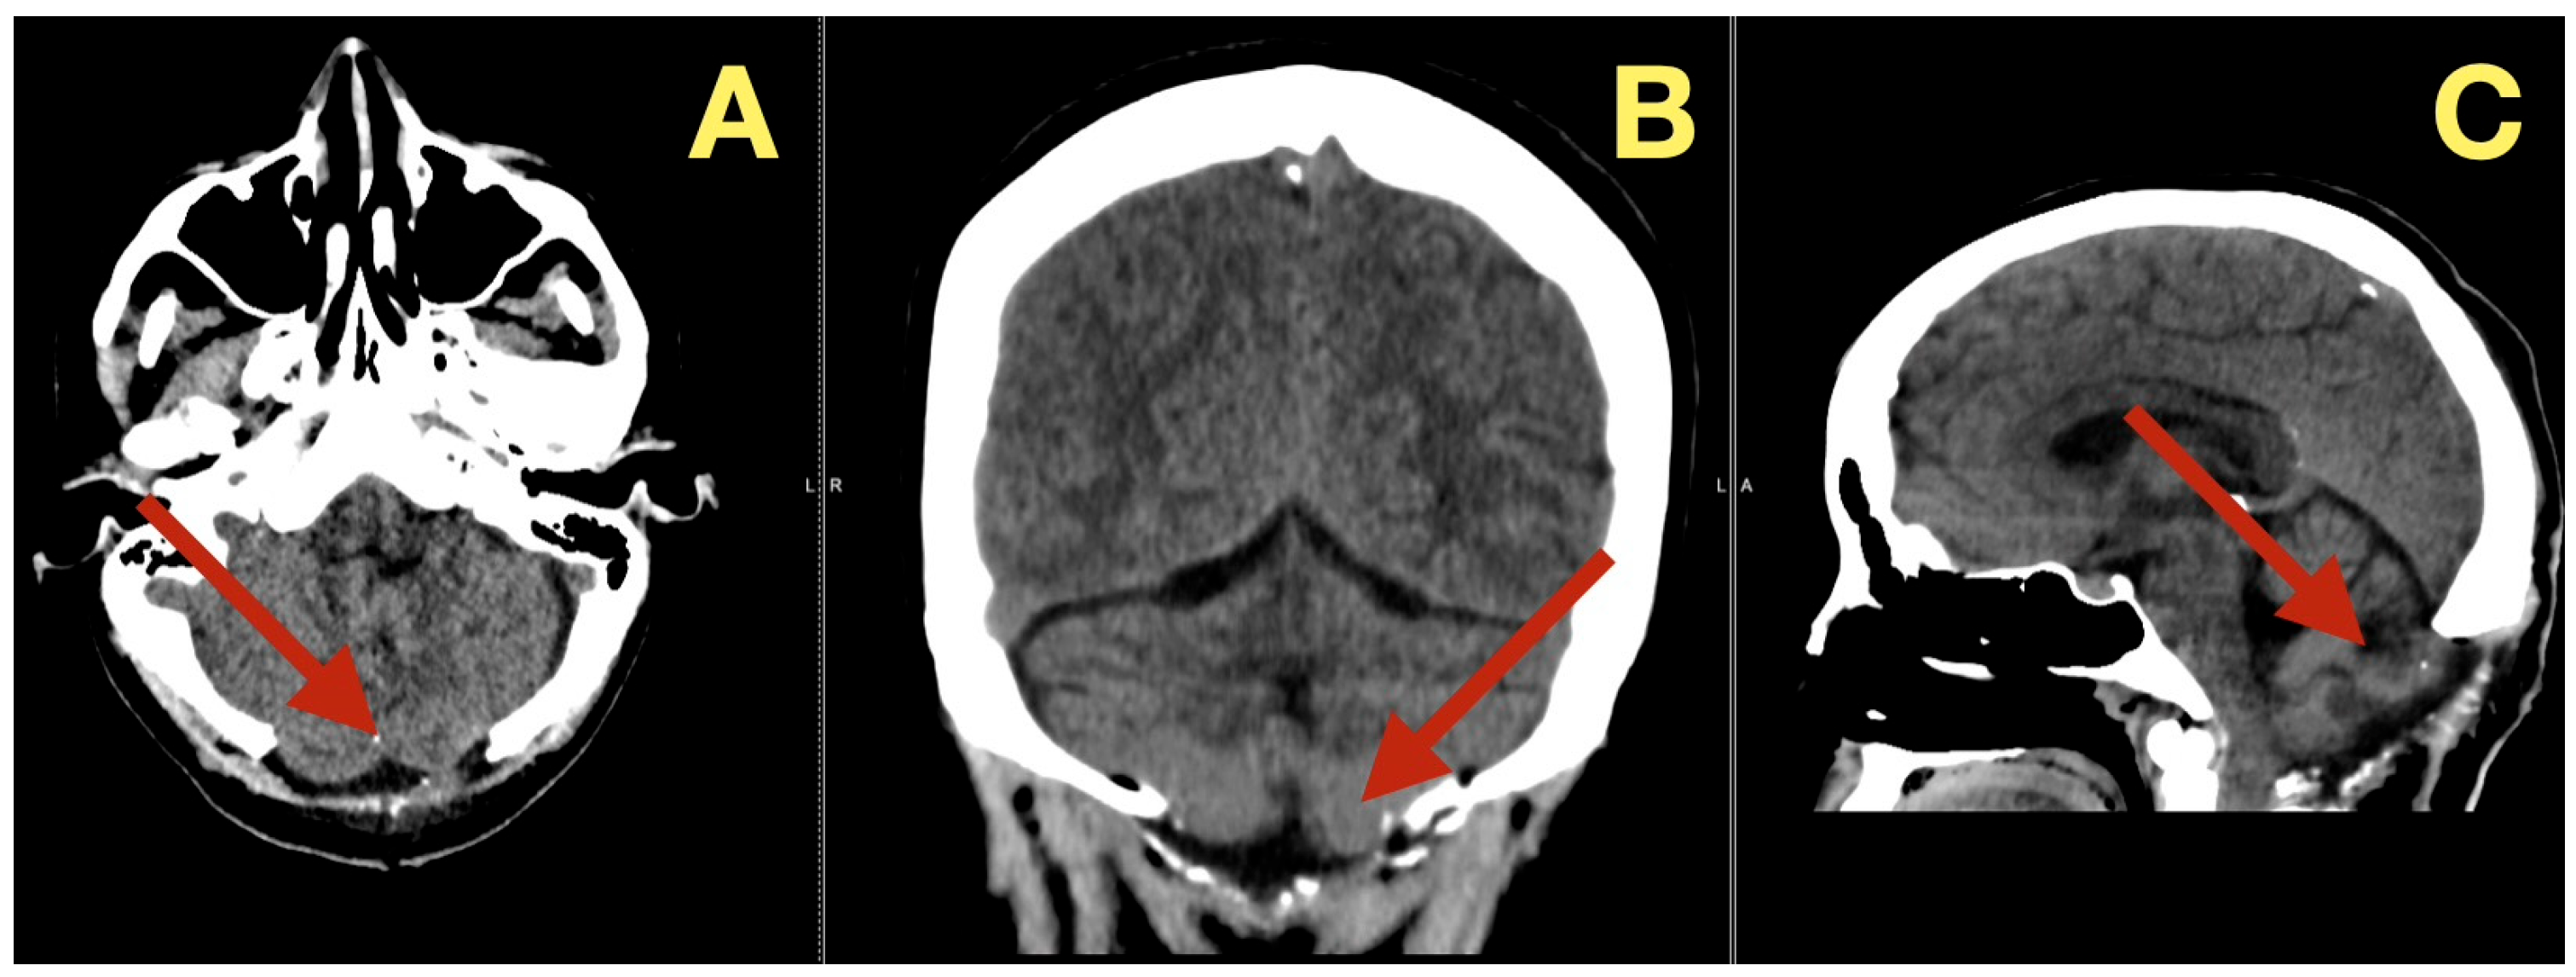

Follow up CT scans three months after surgery (Figure 6), confirmed continued decompression of the fourth ventricle and structural stability, as evidenced by stable size of the fourth ventricle, open CSF pathways, and absence of inflammation or scarring. The patient was clinically normal and able to resume all normal activities

Figure 6.

Three-month postoperative CT scan. (A): Axial CT revealing sustained decompression of the fourth ventricle and preservation of the posterior-fossa configuration (arrow). (B): Coronal CT showing symmetrical cerebellar folia and patent lateral recesses without evidence of recurrent mass (arrow). (C): Sagittal CT confirming persistent brainstem relaxation, patent foramen of Magendie, and absence of postoperative scarring (arrow).

CT scans seven months after surgery (Figure 8), demonstrated long term stability: the fourth ventricle remained widely patent, the posterior fossa proportions were normal, the CSF spaces were symmetric, and there was no evidence of recurrence, new calcification, subdural collection, or ventricular change. Clinically she remained neurologically intact, describing stable gait and effortless balance. Final scores were MRS = 0, SARA = 1/40, and she returned to work and daily activity.

Figure 8.

Seven-month postoperative CT scan. (A): Axial CT showing persistent decompression of the fourth ventricle and normal CSF distribution (arrow). (B): Coronal CT demonstrating stable midline anatomy and unchanged posterior-fossa dimensions with no residual lesion (arrow). (C): Sagittal CT confirming complete restoration of brainstem and cerebellar geometry, maintained CSF flow, and absence of new pathology (arrow).